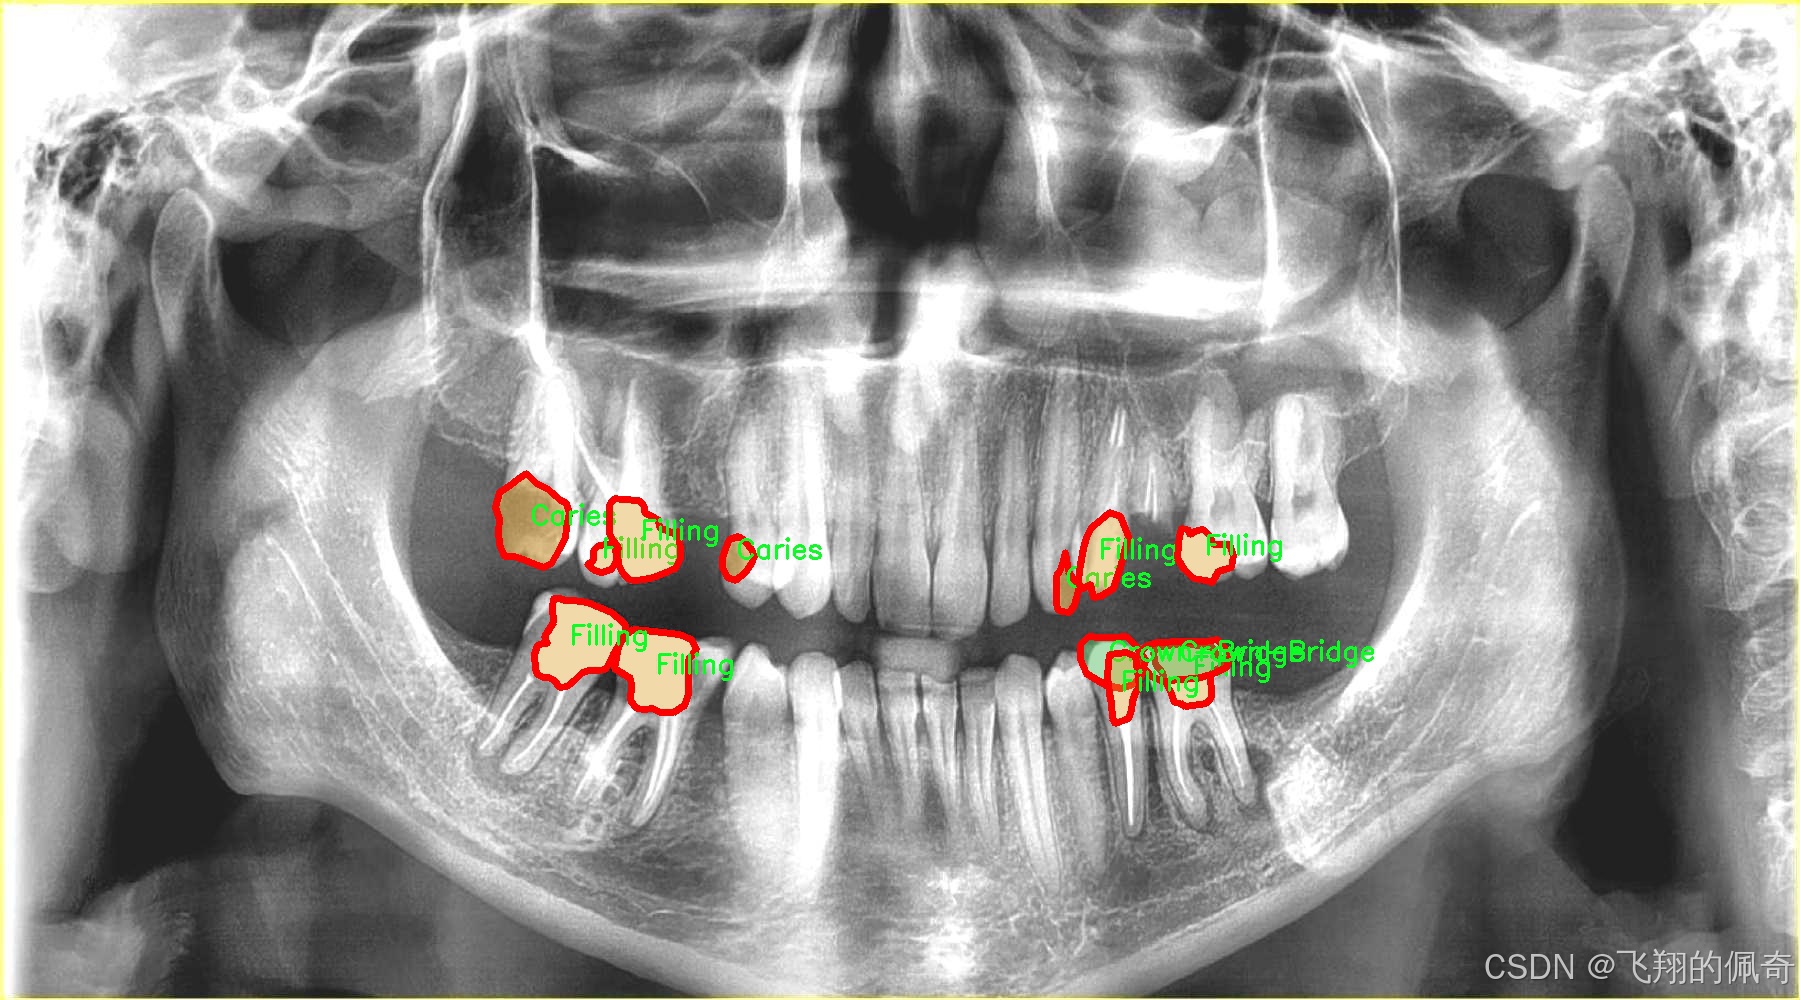

图片效果

在现代牙科医学中,龋齿的早期诊断与治疗至关重要,而图像分割技术在这一领域的应用为牙科医生提供了更为精确的工具。为此,我们构建了一个名为“tooth segmentation”的数据集,旨在训练改进版的YOLOv8-seg模型,以实现对牙齿病变图像的高效分割。该数据集专注于八种不同的牙齿病变类型,涵盖了从龋齿到各种修复体的多样性,确保模型能够识别和分割这些关键特征。

“tooth segmentation”数据集包含八个类别,分别为:龋齿(Caries)、牙冠与桥(Crown-Bridge)、填充物(Filling)、植牙(Implant)、后螺钉(Post-screw)、根管填充(Root canal Obturation)、牙冠(crown)以及再植体(implant)。这些类别不仅代表了牙齿的不同病变状态,还涵盖了牙科治疗中常见的修复和重建过程。这种多样性使得数据集在训练过程中能够有效地提高模型的泛化能力,帮助其在实际应用中更好地适应不同的病例。